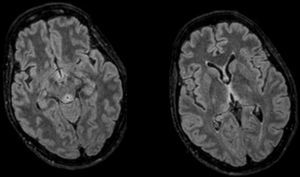

A su llegada constatamos un GCS entre los 8-12 puntos. Su única focalidad física era la inexistencia de reflejos oculocefálicos. Ante la clínica, cronopatología y negatividad de las pruebas, la sospecha inicial incluyo la posibilidad de EW, administrándose tiamina intravenosa, 24-48h más tarde, presentó una mejoría evidente, mostrándose bradipsíquica pero consciente y colaboradora. Se realizó una resonancia magnética (RM) craneal, observándose lesiones simétricas hiperintensas periacueductales, talámicas, cuerpos mamilares y tubérculos cuadrigéminos, hallazgos característicos de la EW, pudiendo ser dada de alta de forma precoz. A pesar de la rápida recuperación inicial, en las revisiones continuadas mantenía algunas secuelas sobre la marcha y la memoria.

El diagnóstico es clínico, aunque existen pruebas para evaluación y apoyo. La RMN cerebral es la prueba de elección1,3 por su especificidad (93%) y valor predictivo positivo (89%), descartándose la TC por su escasa sensibilidad. Las lesiones típicas son simétricas y afectan al tálamo medial, cuerpos mamilares, placa tectal y región periacueductal8, como en nuestro caso (fig. 1). El déficit de tiamina puede analizarse mediante cromatografía líquida de alta resolución o a partir de la actividad de la transcetolasa eritrocitaria1,3,7, donde actúa como cofactor. En nuestra paciente no pudimos obtener niveles ya que un error de extracción inutilizó la muestra. La rápida recuperación tras la administración es el mejor diagnóstico, como en nuestra paciente1,3,7.